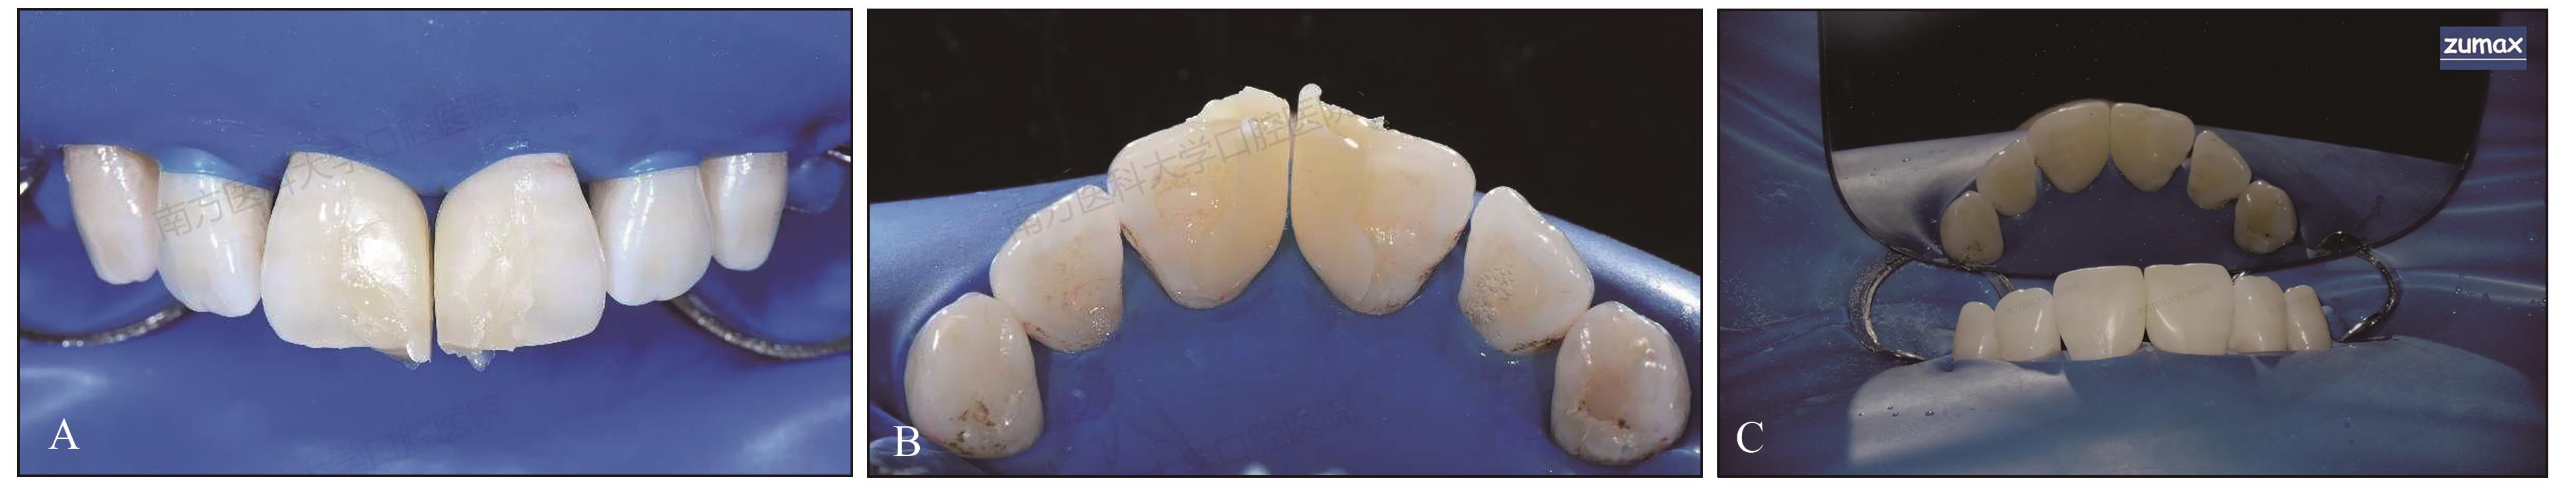

图 4

治疗过程A:比色;B:测量间隙大小;C:去除牙菌斑;D:酸蚀;E:涂布粘接剂;F:放置成型片:接触点与21牙切端垂直距离约7.5 mm,成型片切端用流体树脂做“W形”的固位体防止成型片移动;G、H、I:注射复合树脂并光固化;J、K、L:修复体修型抛光。"